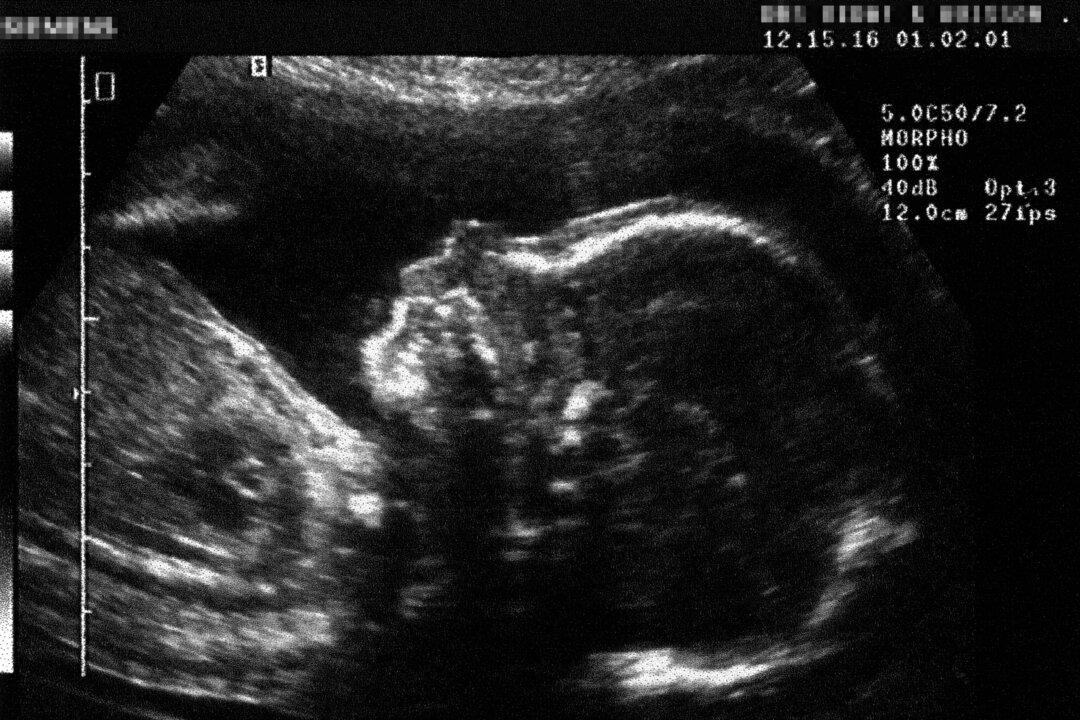

A bill proposing the establishment of a committee to assess the sentience of unborn babies and embryos should afford them rights equivalent to those enjoyed by animal foetuses, according to a Conservative peer.

On Friday the House of Lords received a second reading of Tory peer Lord Moylan’s proposals for a bill to “make provision for a Foetal Sentience Committee to review current understanding of the sentience of the human foetus and to inform policy-making.”